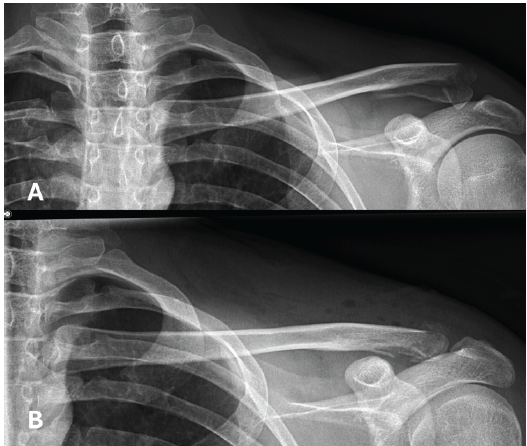

Conventional radiographs and a CT scan revealed a very distal, multifragmentary, and dislocated clavicle fracture (Fig. 1). Due to the highly comminuted distal configuration, the lateral bone stock was severely compromised. The fracture was classified as Jäger-Breitner Type IIa and Neer Type V. No further associated injuries were identified.

Figure 1: A: X-ray showing a dislocated, multifragmentary lateral clavicle fracture after the first accident. B: X-ray imaging performed one day postoperatively.